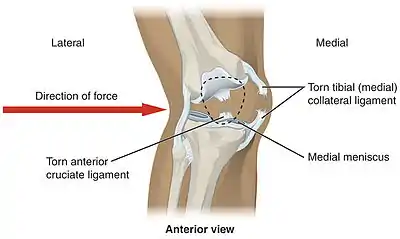

Common injuries due to physical activity

In sports that place great pressure on the knees, especially with twisting forces, it is common to tear one or more ligaments or cartilages. Some of the most common knee injuries are those to the medial side: medial knee injuries.[29]

Anterior cruciate ligament injury

The anterior cruciate ligament is the most commonly injured ligament of the knee. The injury is common during sports. Twisting of the knee is a common cause of over-stretching or tearing the ACL. When the ACL is injured a popping sound may be heard, and the leg may suddenly give out. Besides swelling and pain, walking may be painful and the knee will feel unstable. Minor tears of the anterior cruciate ligament may heal over time, but a torn ACL requires surgery. After surgery, recovery is prolonged and low impact exercises are recommended to strengthen the joint.[30]